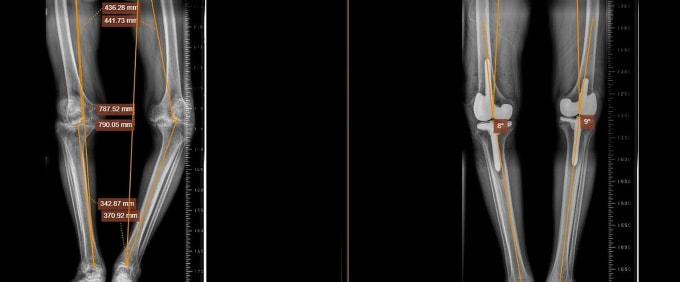

Ông Tri phẫu thuật tái tạo dây chằng chéo trước ở chân trái hơn 10 năm trước, sau đó khớp gối không ổn định, hai chân cong vẹo. Ông điều trị bằng nhiều phương pháp như dùng thuốc theo đường uống, tiêm, tập vật lý trị liệu... Kết quả chụp X-quang tại Bệnh viện Đa khoa Tâm Anh TP HCM cho thấy ông Tri bị thoái hóa khớp gối nặng cả hai chân, chân trái vẹo trong hơn 30 độ và chân phải vẹo ngoài hơn 10 độ. Bệnh kéo dài làm sụn khớp gần như không còn, khiến các đầu xương bị cọ xát, gây mất xương, co rút dây chằng trong và thay đổi trục khớp gối, dẫn đến biến dạng chân.

Trước phẫu thuật, ông được kiểm soát chặt chẽ các bệnh lý nền để giảm nguy cơ biến chứng, chụp CT hơn 100.000 lát cắt 3D để tạo ra hình ảnh 3D chi tiết của khớp gối, quan sát toàn diện cấu trúc xương khớp, xác định vị trí và mức độ thiếu xương, các tổn thương tiềm ẩn khác. Sau đó, bác sĩ Dương sử dụng phần mềm TraumaCAD chuyên dụng trong phẫu thuật chỉnh hình để đo đạc và lựa chọn khớp háng có kích thước phù hợp với cơ thể người bệnh.

Trong quá trình phẫu thuật, bác sĩ loại bỏ rất nhiều tổ chức gout, viêm ở bao hoạt dịch, dây chằng... làm sạch bên trong khớp gối, sau đó thay khớp nhân tạo semi constrained. Đây là loại khớp có độ ổn định cao, giải phóng dây chằng bên trong đang bị co rút nhưng vẫn đảm bảo dây chằng bên ngoài không bị quá căng. Cấu trúc khớp được thiết kế đặc biệt, có khả năng thay thế chức năng của phần xương đã mất. Người bệnh còn được chỉnh lại trục chi, khôi phục hình dáng và khả năng vận động của hai chân.